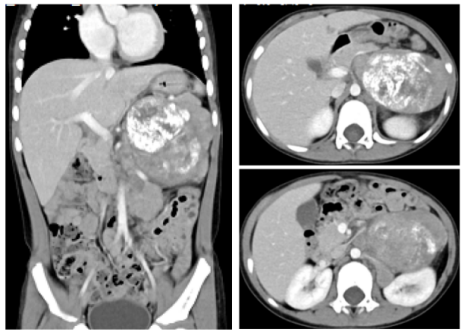

外院化疗前CT

左上腹膜后腹主动脉左旁一巨大肿块影,约7.2 ×5.3 ×8.3 cm,腹主动脉左旁及左肾上腺多个结节状软组织影,考虑神经母细胞瘤(图1)。

图1:外院治疗前CT